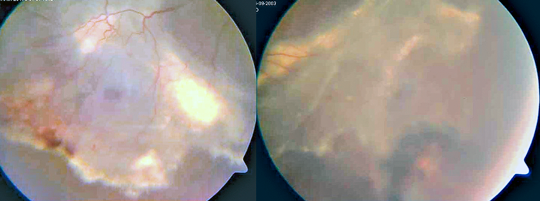

8-12 Familyal eksudatif vitreoretinopati hastasında geç dönemde traksiyon bantları ve periferde eski avasküler retina bölgesine ait demarkasyon hattı. Hastada prematürite ve düşük doğum ağırlığı öyküleri mevcut değil (Prof. Dr. Sibel Kadayıfçılar, Prof. Dr. Bora Eldem’in izniyle).

Pa­tog­no­mo­nik anor­mal vit­re­us ya­pı­sı­na ge­nel­lik­le kon­je­ni­tal iler­le­me­yen yük­sek mi­yo­pi, pa­ra­vas­kü­ler pig­ment­li la­tis de­je­ne­ras­yo­nu, ka­ta­rakt ve re­ti­na de­kol­ma­nı eş­lik eder (Şekil 8-13). Yüz­de or­ta hat ya­rı­ğı, mik­rog­na­ti, düz or­ta yüz ve ba­sık bu­run kö­kü, sa­ğır­lık gö­rü­le­bi­lir.

8-13 Stickler sendromu (Prof. Dr .Sibel Kadayıfçılar, Prof. Dr. Bora Eldem’in izniyle).